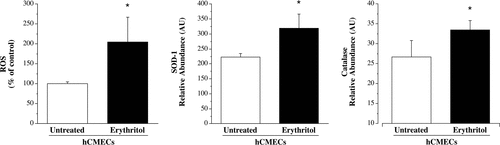

Investigadores de la Universidad de Colorado Boulder analizaron cómo el eritritol afecta las células de los vasos sanguíneos del cerebro. Utilizaron una dosis equivalente a la que se encuentra en una bebida común (~30 g), y la aplicaron durante 3 horas en un modelo celular. Los resultados fueron contundentes: las células expuestas produjeron casi el doble de especies reactivas de oxígeno (ROS), lo que indica un fuerte aumento del estrés oxidativo. Además, disminuyó la producción de óxido nítrico, una molécula clave que permite que los vasos se relajen y mantengan una circulación adecuada.

El problema no es solo teórico. La alteración de la función endotelial cerebral puede afectar la circulación y comprometer el flujo sanguíneo al cerebro. Cuando los vasos no se dilatan correctamente, aumenta la probabilidad de sufrir un evento isquémico. El estudio también reveló que las células expuestas al eritritol mostraron un aumento en enzimas antioxidantes, lo que sugiere un intento del organismo por defenderse ante un entorno oxidativo hostil.